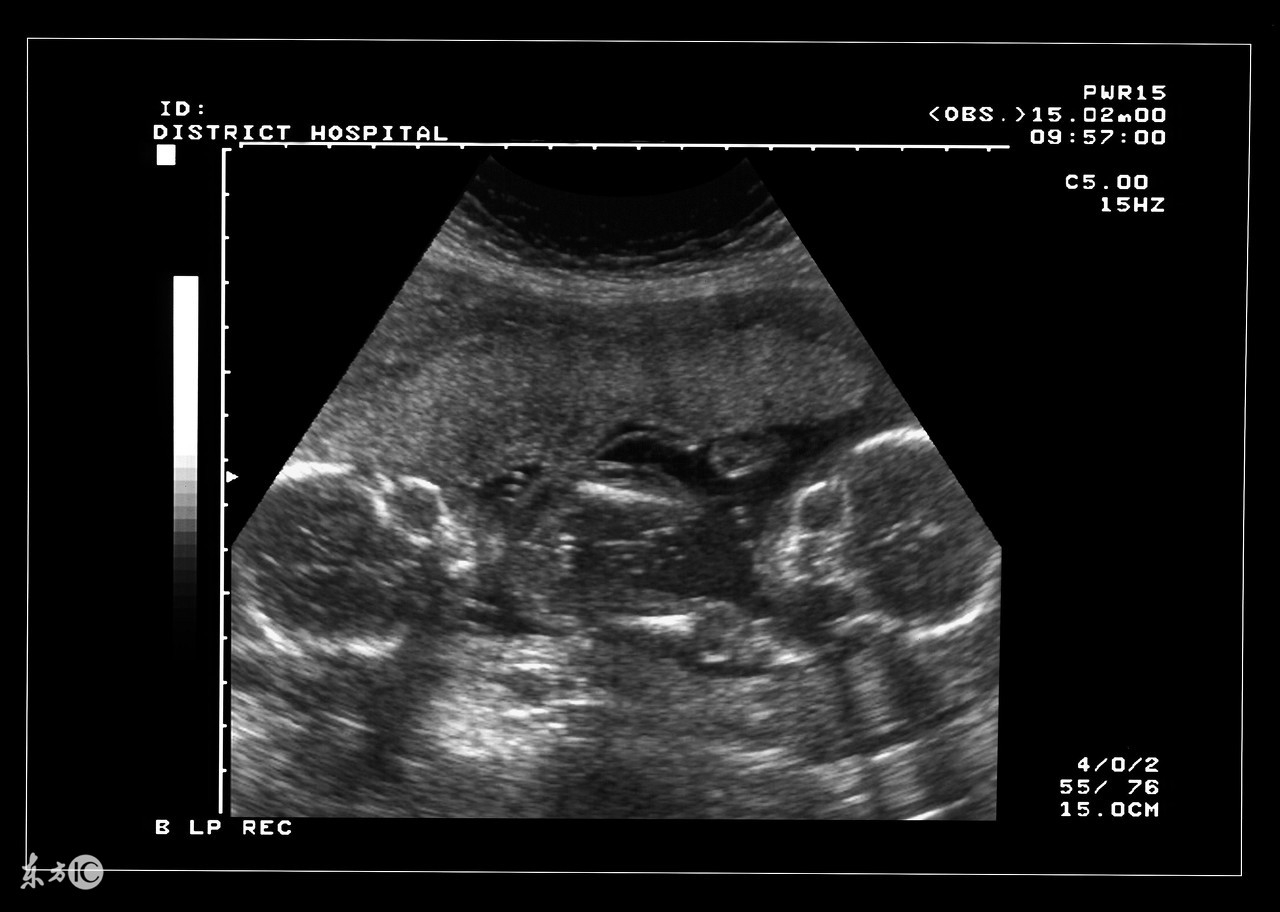

双胞胎确实是一件可想而不可求的事情,当孕妇怀上双胞胎或者多胎后,使母体长期处于超负荷的状态,在预产期到来之前,准妈妈需要就是否实施剖腹产的问题预先与家人和医生达成一致,并为此做好准备。大家都知道,自然分娩是最理想不过的,但实际上为了确保安全,大部分多胞胎最终实施的都是剖腹产。

双胎妊娠检查非常重要。因为双胎孕妇比一般孕妇子宫明显增大,这不仅增加了孕妇身体的负担,还因为对其心、肺及下腔静脉的压迫而容易产生心慌、呼吸困难及下肢浮肿等不适。双胎妊娠出现妊娠合并症者也较多,其妊高娠的发生率明显高于一胎妊娠,所以双胎妊娠者要听从医嘱,按期去医院接受检查。

双胎妊娠因为子宫腔相对狭窄胎盘血液循环障碍,其流产发生率较单胎妊娠高2—3倍,因此应加强孕期保护与监护。若一胎发生死胎,另一胎仍可继续生长发育,死亡的胎儿将被吸收或挤压成纸样儿随正常胎儿娩出,不必担心害怕,更不要引产终止妊娠。因双胎妊娠子宫过度膨胀,易发生早产,故应于中期妊娠后注意休息,避免房事,并提前4周做好分娩前的准备工作。因为妊娠的并发症尤其是妊高娠的发生率比较高,从母子安全考虑,应在预产期即住院待产,以免发生早产或其他不测。